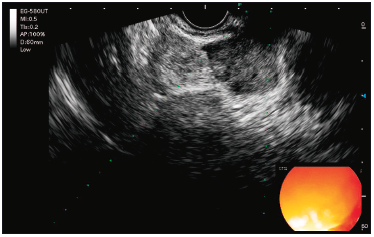

Se realizó una colonoscopía que identificó una lesión subepitelial rectal. La USE subsiguiente reveló una lesión subepitelial en el recto medio-inferior, de aproximadamente 10 mm x 15 mm, originada en la cuarta capa ecogénica (muscular propia), continua con una formación nodular mesorrectal de 21 mm x 15 mm. También se observaron ganglios linfáticos mesorrectales regionales de 5 mm a 6 mm (Figura 1 y 2).

Figura 1. Lesión originada en la cuarta eco capa (muscular propia) en

mesorrecto